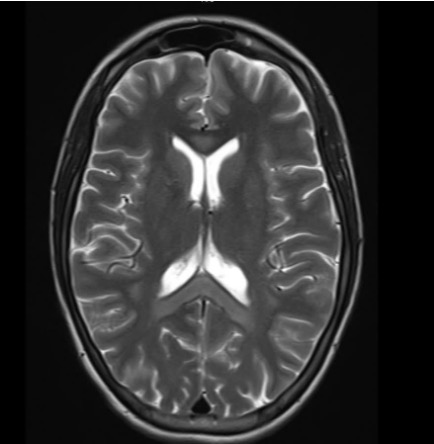

3 ngày trước khi nhập viện, bệnh nhân sử dụng bóng cười với tần suất cao hơn bình thường, dẫn đến diễn biến bệnh lý cấp tính với biểu hiện mất ngôn ngữ, tổn thương não bộ trên diện rộng. Kết quả chụp cộng hưởng từ (MRI) sọ não cho thấy tổn thương lan tỏa hai bán cầu và thể chai.

Hình ảnh tổn thương lan tỏa hai bán cầu não và thể chai của nữ bệnh nhân C. (Ảnh: Bác sĩ cung cấp)